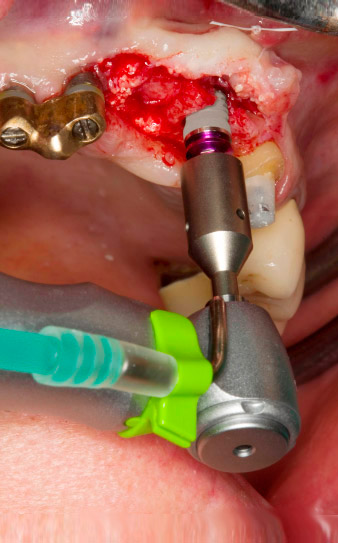

le forage pilote est effectué avec le nouvel Implantmed et le contre-angle WS-56 L

Fig. 2 : Deux mois plus tard, le forage pilote est effectué avec le nouvel Implantmed et le contre-angle WS-56 L (programme P1, ratio 1:1). Le refroidissement est effectué au moyen de la buse de pulvérisation située à gauche (pour les utilisateurs droitiers).